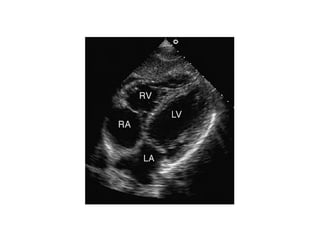

APICAL 4 CHAMBER VIEW

FALSE TENDON IN LV APEX

MODERATOR BAND IN RV APEX